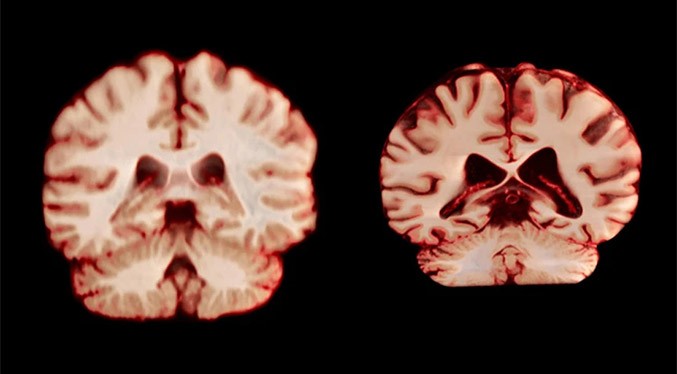

Un nuevo estudio sobre las implicaciones que las diferencias de género en el envejecimiento cerebral tienen en el alzhéimer revela que los hombres experimentan una mayor reducción de volumen en más regiones del cerebro que las mujeres, recoge la revista Nature.

Tras examinar las diferencias de tamaño cerebral basadas en el sexo, el equipo descubrió que los hombres mostraban un deterioro en un mayor número de regiones cerebrales, incluidas muchas partes de la corteza, a edades más avanzadas.